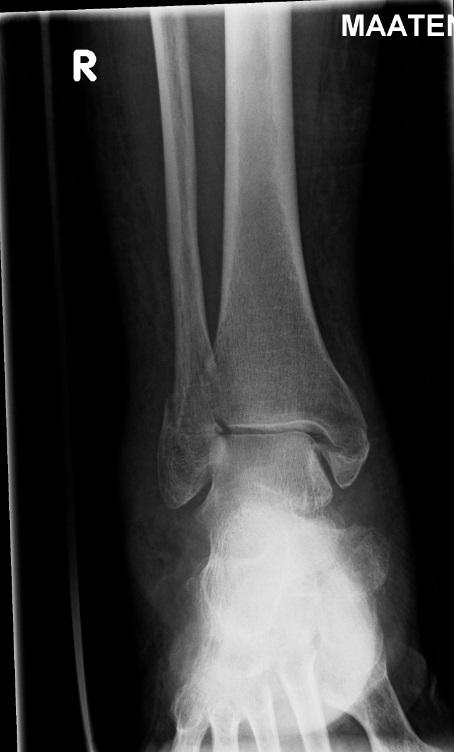

image: X-ray image of a fractured ankle.